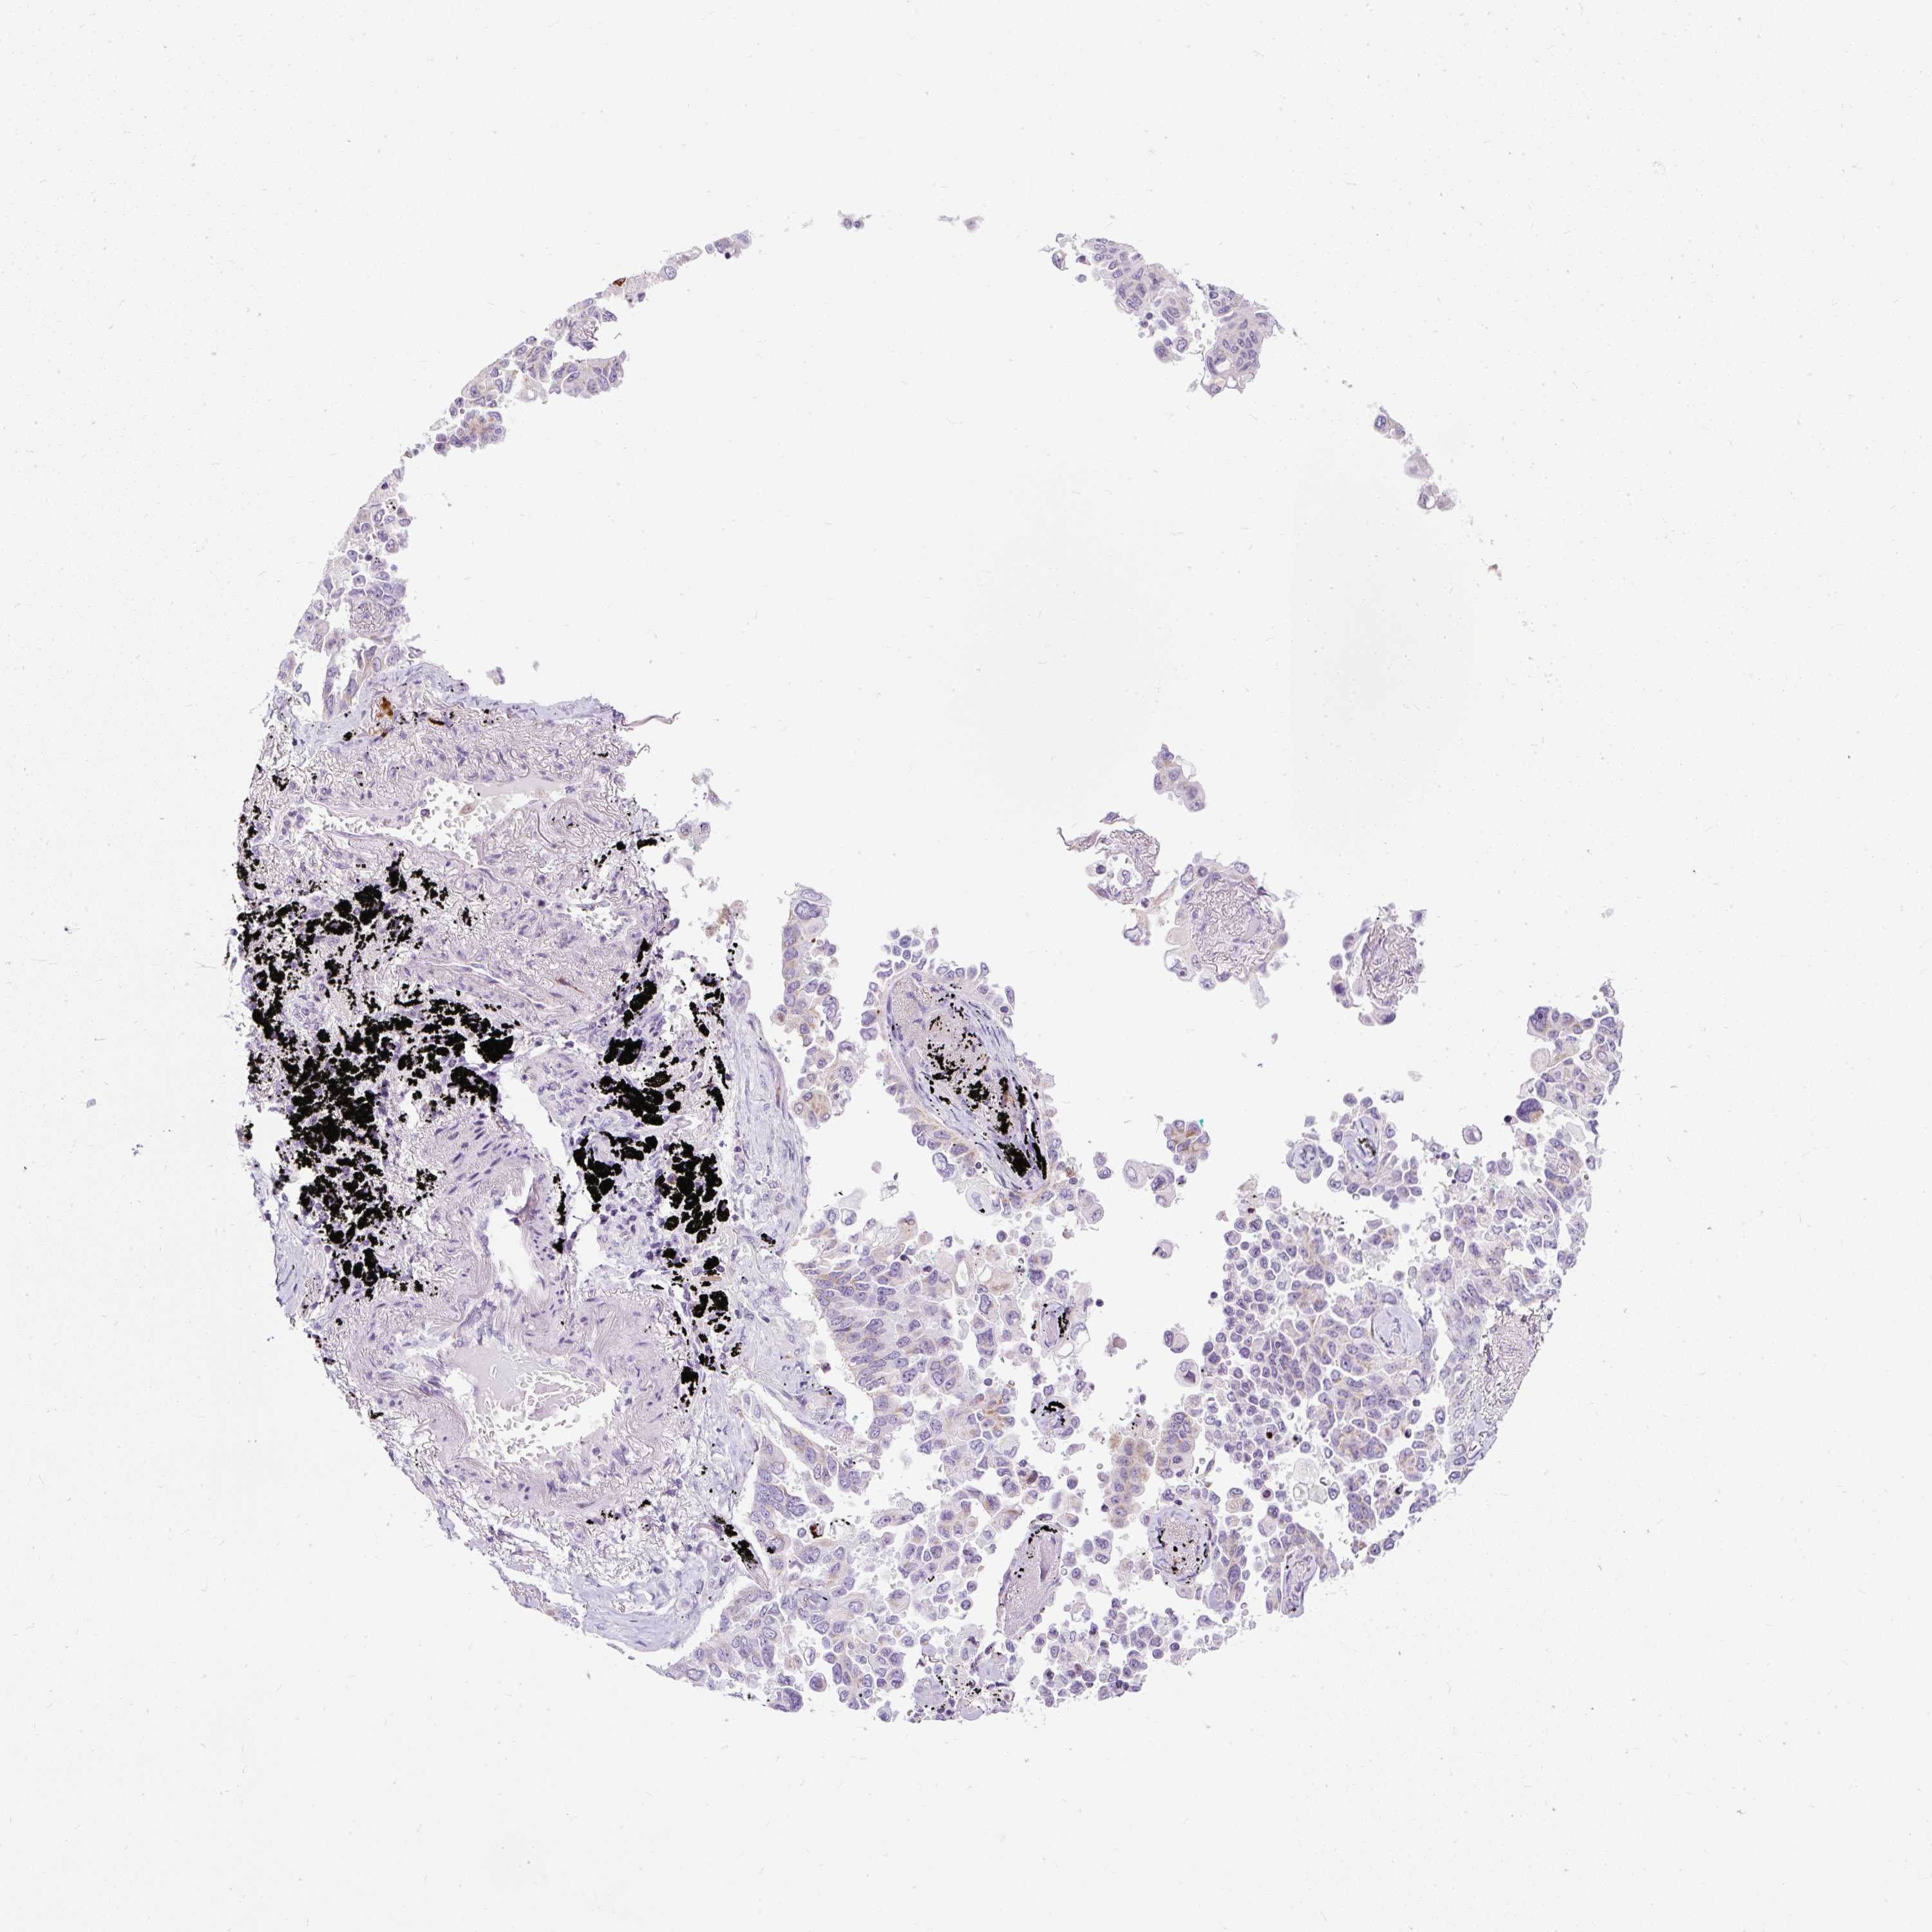

LUNG SQUAMOUS CELL CARCINOMA (TCGA) - Interactive survival scatter ploti

The Survival Scatter plot shows the clinical status (i.e. dead or alive) for all individuals in the patient cohort, based on the same data that underlies the corresponding Kaplan-Meier plots. Patients that are alive at last time for follow-up are shown in blue and patients who have died during the study are shown in red.

The x-axis shows the expression levels (FPKM) of the investigated gene in the tumor tissue at the time of diagnosis. The y-axis shows the follow-up time after diagnosis (years). Both axes are complimented with kernel density curves demonstrating the data density over the axes. The top density plot shows the expression levels (FPKM) distribution among dead (red) and alive patients (blue). The right density plot shows the data density of the survived years of dead patients with high and low expression levels respectively, stratified using the cutoff indicated by the vertical dashed line through the Survival Scatter plot. This cutoff is automatically defined based on the FPKM cutoff that minimizes the p-score. The cutoff can be changed by dragging the vertical line or by entering a cutoff value in the square labeled "Current cut-off".

Under the Survival Scatter plot the p-score landscape (black curve; left axis) is shown together with dead median separation (red curve; right axis). Dead median separation is the difference in median mRNA expression between patients who have died with high and low expression, respectively. It is calculated as follows: median FPKM expression of dead patients with high expression - median FPKM expression of dead patients with low expression. This is intended to aid the user in visually exploring custom cutoffs and the associated p-scores and dead median separation.

Individual patient data is displayed and can be filtered by clicking on one or more of the category buttons on the top of the page. Categories describing expression level and patient information include: high, low, alive, dead, female, male and tumor stages. The scale of the x-axis can be toggled between linear and log-scale by clicking on the "x log" button. Mouse-over function shows TCGA ID, patient information and mRNA expression (FPKM) for each patient.

& Survival analysisi

Kaplan-Meier plots summarize results from analysis of correlation between mRNA expression level and patient survival. Patients were divided based on level of expression into one of the two groups "low" (under cut off) or "high" (over cut off). X-axis shows time for survival (years) and y-axis shows the probability of survival, where 1.0 corresponds to 100 percent.

FMC1 is not prognostic in Lung Squamous Cell Carcinoma (TCGA)

Best expression cut offi

Based on the FPKM value of each gene, patients were classified into two groups and association between prognosis (survival) and gene expression (FPKM) was examined. The best expression cut-off refers the FPKM value that yields maximal difference with regard to survival between the two groups at the lowest log-rank P-value. Best expression cut-off was selected based on survival analysis .

When clicking on this number, the vertical dashed line indicating cut-off, the interactive survival plot, and the Kaplan-Meier curve will be adjusted to show results based on the best expression cut-off.

: 16.39

Median expressioni

Median expression refers to the median FPKM value calculated based on the gene expression (FPKM) data from all patients in this dataset. When clicking on this number, the vertical dashed line indicating cut-off, the interactive survival plot, and the Kaplan-Meier curve will be adjusted to show results based on the median expression.

: N/A

Median follow up timei

Median follow up time refers to the median time (years) after diagnosis with this type of cancer, based on clinical data from all patients in this dataset.

P scorei

Log-rank P value for Kaplan-Meier plot showing results from analysis of correlation between mRNA expression level and patient survival.

N/A

5-year survival highi

5-year survival for patients with higher expression than the expression cutoff.

For melanoma and glioma, 3-year survival is shown.

5-year survival lowi

5-year survival for patients with lower expression than the expression cutoff.

TCGA RNA samplesi

RNA-seq data is reported as average FPKM (number Fragments Per Kilobase of exon per Million reads), generated by the The Cancer Genome Atlas (TCGA) .

Normal distribution across the dataset is visualized with box plots, shown as median and 25th and 75th percentiles. Points are displayed as outliers if they are above or below 1.5 times the interquartile range. FPKM values of the individual samples are presented next to the box plot.

Average pTPM 12.1

Number of samples 489